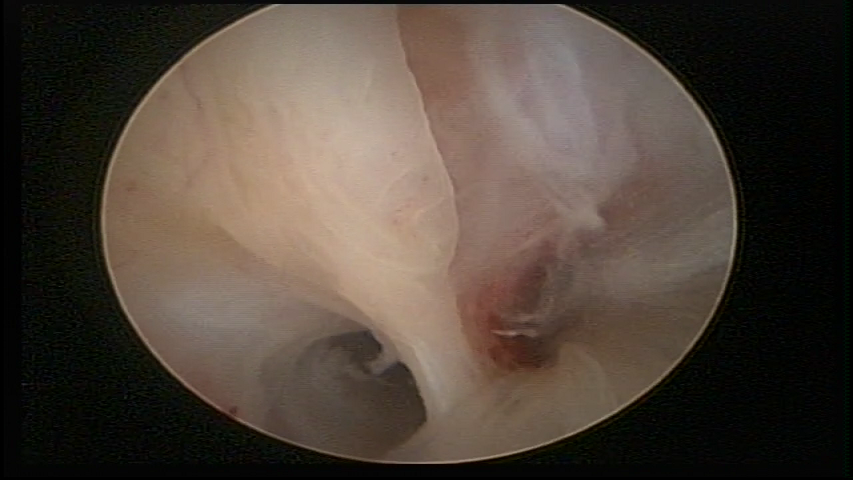

Bicornuate uterus

Malformation in which there is the lack of the flat portion of uterine fundus due to the lack of fusion on the proximal portion of paramesonephric ducts. The uterine fundus has two narrowed spaces in a divergent oblique angulation. It may be complete, from the fundus to the cervix; or partial, completely dividing the uterine cavity.

The tilted uterus which presents the most difficult hysteroscopic diagnosis occurs when there is only a small indentation of the uterine fundus.